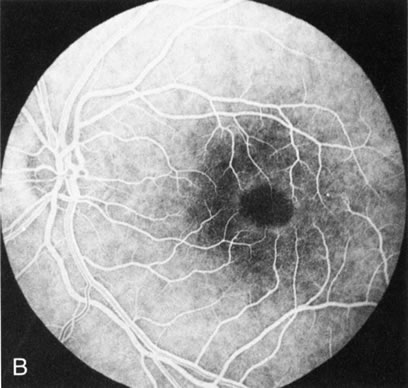

In retinitis pigmentosa (RP), the pigment abnormalities of atrophy, migration, and clumping are made apparent by transmitted hyperfluorescence and blocked hypofluorescence (Fig. 1A). Patients who have very minimal pigmentary alterations (pauci pigmentary RP) or no pigment abnormalities (RP sine pigmento) may show the abnormalities on fluorescien angiography (FA). It is uncommon to see choriocapillaris atrophy except in the late stages. This finding corresponds to the histopathology, which shows that the earliest abnormalities are in the photoreceptors and that the choroid is normal.1

Fig. 1. Retinitis pigmentosa. A. A typical area of bone spicule pigmentation. B. Diffuse dye leakage is apparent throughout the posterior pole. C. The early angiogram shows dilated and irregular retinal radial peripapillary capillaries and perifoveal retinal capillaries. D. Leakage from these vessels are evident in the late angiogram.

Dye leakage in RP may occur from the retinal vessels or at the level of the retinal pigment epithelium (Fig. 1B).2–4 The leakage may be seen in the macula and posterior pole, along the vascular arcades in the distribution of the radial peripapillary capillaries, and in the periphery (where an exudative vasculopathy resembling Coats' disease is suggested).

Of more clinical importance is the role of FA in the diagnosis and treatment of cystoid macular edema (CME) (Fig. 1C and D). Stereoscopic FA indicates that the leakage, which may be diffuse or have the typical petaloid stellate appearance of CME, can come from the perifoveal retinal capillaries, from the choroid through the RPE, or from a combination of both sources.4 With the recent suggestion that CME in RP may be successfully treated with acetazolamide,5, 6 FA is thus important to document the diagnosis of CME, establish the origin(s) of leakage, and follow patients during and after therapy.